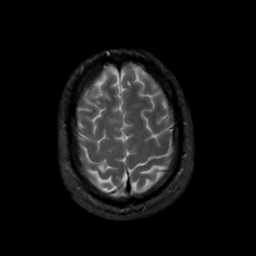

MR Study #10, April 28, 1991 -- Slice #42